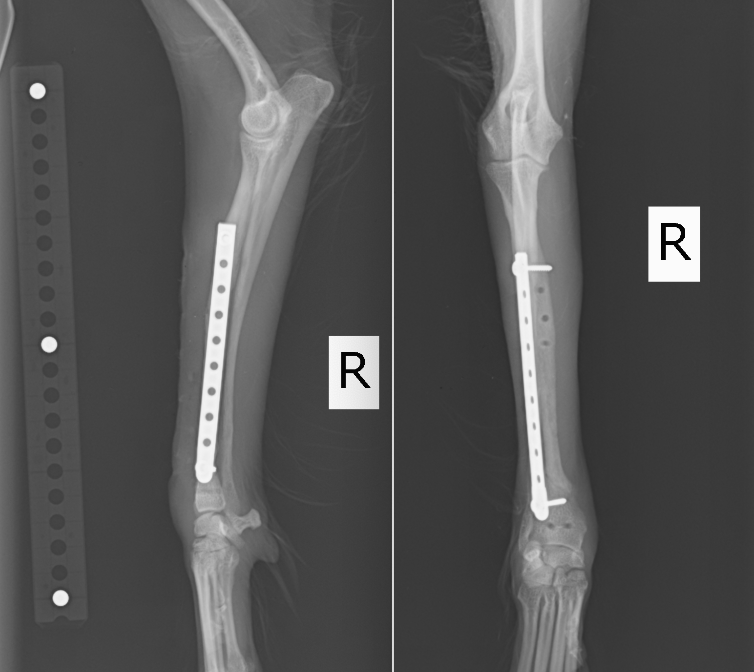

イタリアングレーハウンドの橈尺骨骨折です。2.0mmスクリューを使用しています。

トイプードル9歳の橈尺骨骨折です。1.5mmスクリューを使用しています。

トイプードル2歳の橈尺骨骨折です。1.5mmスクリューを使用しています。 上の3症例ともにやや中央寄りの先端部の橈尺骨の横骨折(遠位骨幹部橈尺骨横骨折)です。直線のプレートを使用しています。